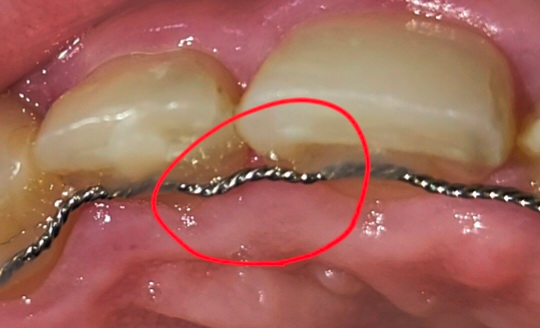

윗니쪽 유지장치에 레진과 레진 사이 철사있잖아요. 그 철사가 어제 밥을 먹다가 튀김이 꼈는데 좀 심하게 꼈는데 아래 사진처럼 그 사이 철사가 들떴더라구요. 혀로 만쟈봤를때 그부분만 살짝 더 날카로운 느낌?이 있구요. 레진이 떨어졌나하고 걱정하면서 몇번 확인해봤는데 레진이 떨어지진 않았어요. 이럴땐 그냥 놨둬도 되나요? 치아에 변형이 생길까요?

• 1번 째 사진